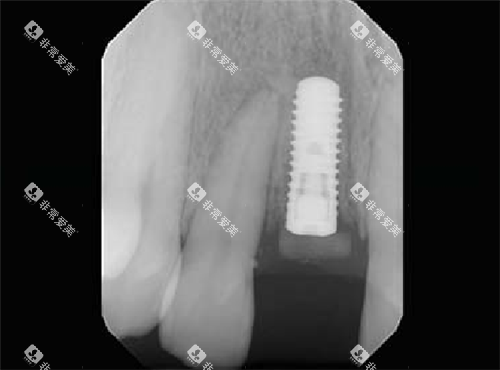

种植牙